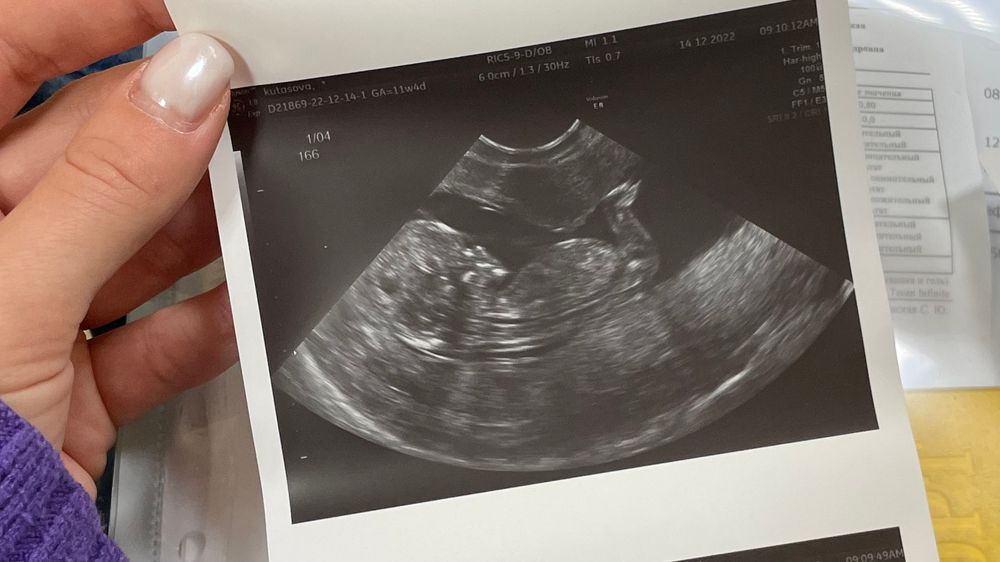

Результаты: УЗИ, КТГ, доплера, скринингаВот нам и 11.4 недель. И первый скрининг:

ЧСС 166;

КТР 57;

БПР 15;

ТВП 1.3;

ПИ 1.04;

Пол - мужской (95%).